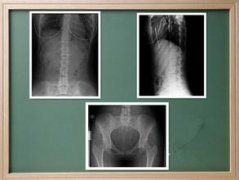

AS ①晚期 ②重度 病史:5年+

- 治疗

治疗后骶髂关节疼痛消失,腰椎前屈、背伸侧弯活动自如,膝关节无压痛感,复查血沉、C反应蛋白、等各项检查均已达到临床康复的标准。